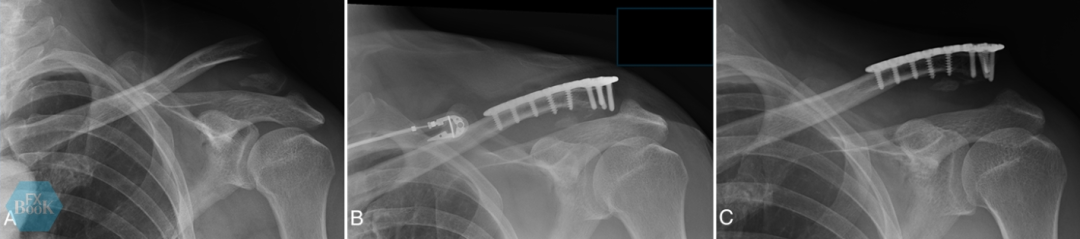

笔者推荐对年轻活跃患者的大多数远端锁骨骨折采用锁定钢板联合喙锁韧带加强固定(图1)。仅在远端骨块严重粉碎或骨质不佳时,才选择钩钢板固定(图2)。

图1, (A)一名29岁男性滑雪受伤导致锁骨远端骨折(Neer V型)平片。(B、C、D、E)术中照片显示采用远端锁骨锁定钢板结合喙锁韧带加强进行切开复位内固定。高强度缝合线环绕喙突(白箭),骨折固定后环绕钢板打结(绿箭)。另在附着喙锁韧带的锁骨下方骨块置入2号高强缝线(黄箭),经锁骨钻孔(灰箭)引出,骨折固定后跨越钢板打结(绿箭)。(F、G)术后3个月X线片显示骨折愈合。(H)3个月临床照片确认关节活动度完全恢复。患者术后3个月重返全面体育运动。